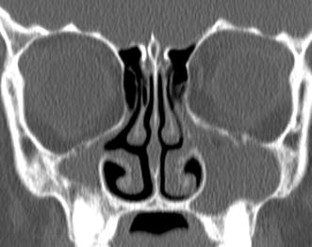

Radiological imaging of inflammatory lesions in the nasal cavity and paranasal sinuses

Paranasal sinus development and pneumatisation variants are described, and rhinosinusitis and different patterns of inflammatory sinonasal diseases are reviewed. Other inflammatory sinonasal diseases, e.g., fungal sinusitis, mucocele, pyocele and sinonasal manifestations in systemic diseases, are briefly described. Computed tomography (CT) is the primary modality in diagnosing and mapping suspected inflammatory sinonasal disease. Magnetic resonance (MR) imaging is complementary to CT if fungal sinusitis, pyocele or malignancy are suspected.